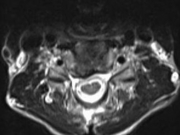

「頚椎症性脊髄症」または一部の「頚椎椎間板ヘルニア」に対して、神経圧迫を取り除くために「除圧術:椎弓形成術」を行います。頚椎の後方より侵入、椎弓を観音開きにし、椎弓スペーサーを挟み込むことにより狭窄した脊柱管を拡大、神経圧迫を取り除きます。操作する椎弓数によりますが、手術時間は40分~1時間で、出血も少なく実施可能です。1週間ほど装着していただく頚椎カラーの支えにより翌日から離床、歩行が可能です。手術後生じる頚の痛み、肩こりの改善に1~2か月要することが難点ですが、成績の安定した実績のある方法です。

![]() 頚椎除圧術術前MRIC5-6 |